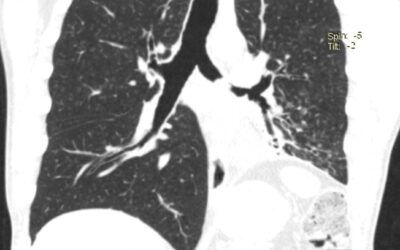

პაციენტი 42 წ მამაკაცი. აქტიური მწეველი. თავს ავად გრძნობს რამოდენიმე თვეა. ჩივილები: ძლიერი ქოშინი ფიზიკურ დატვირთვაზე, ჰაერის უკმარისობა, საერთო სისუსტე. გულმკერდის კტ კვლევით - ორივე ფილტვის ზედა წილებში გაიშვიათებული ფილტვის ქსოვილი, გიგანტური ბულები 10-14 სმ...